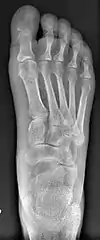

Primus varus deformity

Primus varus deformity is the leaning of the first metatarsal bone away from the second metatarsal and towards the opposite foot (Fig. 1). As it leans over, its head sticks out to form the bunion bump and it also widens the forefoot to cause shoes feeling too tight. Thus when bunion pain becomes unmanageable, surgical correction is to narrow the forefoot by repositioning of the first metatarsal head back to its normal position. This can be done by osteotomy (bone-breaking), soft tissue (non-osteotomy) or fusion techniques.